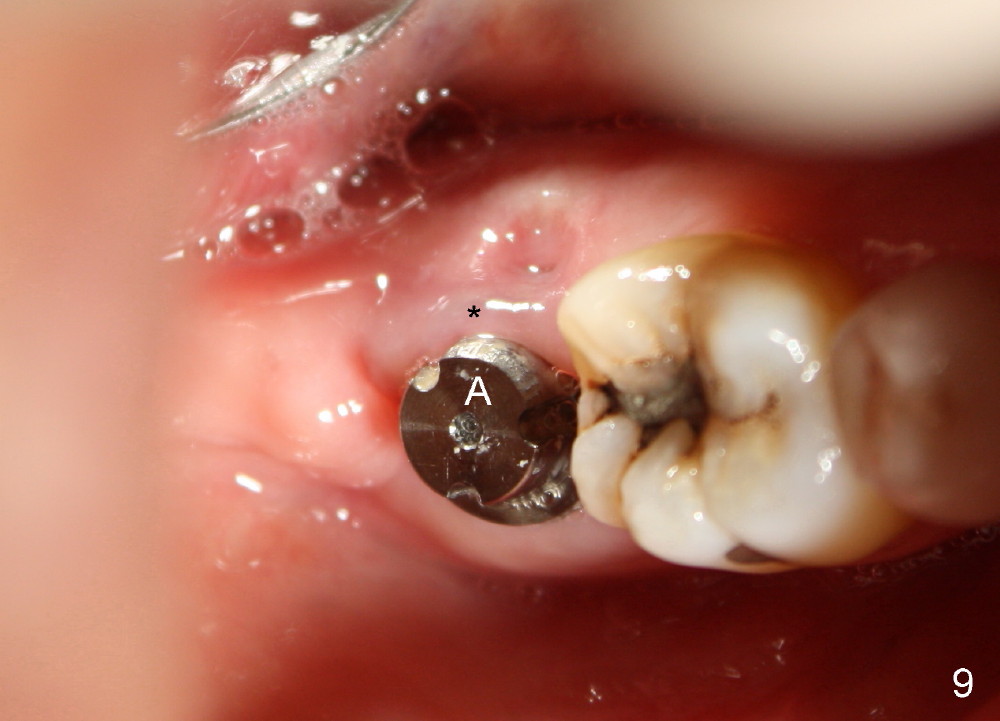

The patient returns 22 days postop (Fig.8-10). The gingiva heals around the implant. There is excess lingual gingiva (Fig.9,10 *), which should recede gradually. Fig.7 is an illustration (from Fig.4) to show how the socket is closed.. A suture is placed (black line) to approximate buccal (black arrow) and lingual (white arrow) gingiva distal to the implant (blue circle).